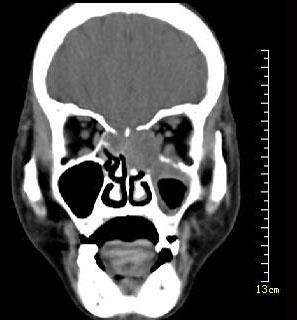

问题 男性50岁,涕中带血半年,体检发现右侧颈部多个硬结,CT扫描如图所示,请选择正确的描述和结论()

选项 A.右侧筛窦内见软组织块影,边缘不规则 B.软组织影累及对侧筛窦、右侧上颌窦 C.右侧眶内壁、上颌窦壁及颅底骨质破坏 D.考虑为右侧筛窦黏液性囊肿 E.考虑为右侧筛窦癌

答案 ABCE